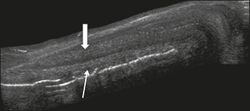

Penile trauma can result from a blunt or penetrating injury, the latter being rarely investigated by imaging methods, almost always requiring immediate surgical exploration. In the erect penis, trauma results from stretching and narrowing of the tunica albuginea, which can undergo segmental rupture of one or both of the corpora cavernosa, constituting a penile fracture.[1]

Figure 4 A: Ultrasound of the penis, right lateral view. Longitudinal section showing rupture of the tunica albuginea with an adjacent 1.92 cm hematoma (between calipers), due to trauma.[1]